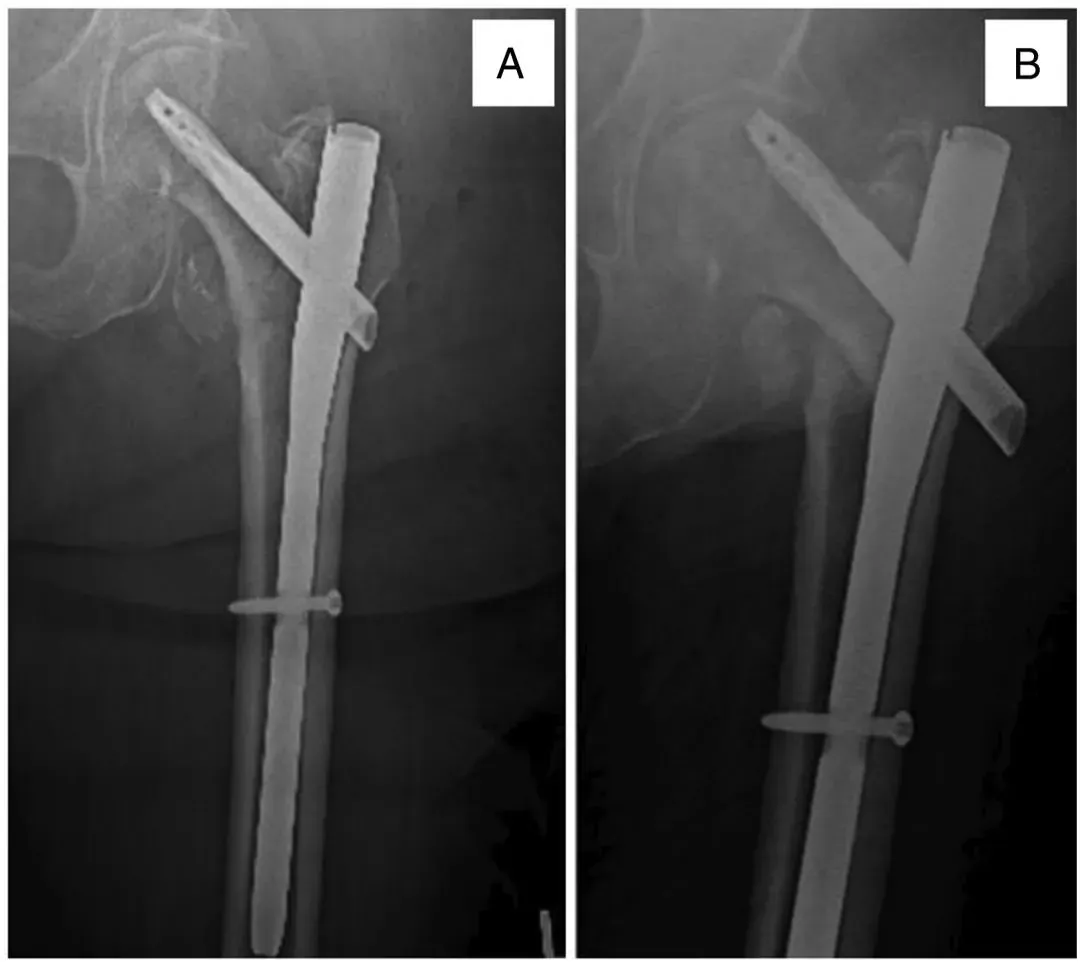

हे एका मोठ्या महानगर क्षेत्रातील आरोग्य सेवा प्रणालीमध्ये असलेल्या दोन संस्थांमध्ये उपचार केलेल्या रुग्णांचे पूर्वलक्षी सर्वेक्षण होते. संस्थात्मक पुनरावलोकन मंडळाच्या मंजुरीनंतर जानेवारी 2018 ते सप्टेंबर 2021 या कालावधीत आयटी फ्रॅक्चरचे प्रारंभिक निर्धारण अयशस्वी झाल्यानंतर सिमेंट-प्रबलित पुनरावृत्ती निर्धारण प्राप्त झालेल्या सर्व रुग्णांसाठी दोन सर्जन (JS आणि BC) च्या केस लॉगची चौकशी करण्यात आली. पुनरावृत्ती शस्त्रक्रियेदरम्यान सिमेंट मजबुतीकरणाचा वापर इलेक्ट्रॉनिक मेडिकल रेकॉर्ड (EMR) ऑपरेटिव्ह रेकॉर्ड आणि पोस्टऑपरेटिव्ह रेडिओग्राफच्या पुनरावलोकनाद्वारे पुष्टी करण्यात आला. आम्ही आयटी फ्रॅक्चरचे प्रारंभिक CMN किंवा SHS फिक्सेशन (आकृती 1) अयशस्वी झाल्यानंतर पुनरावृत्ती फिक्सेशनमध्ये सिमेंट मजबूत होण्याची चिन्हे असलेल्या सर्व रुग्णांना समाविष्ट केले. आम्ही फेमोरल नेक किंवा सबट्रोकाँटेरिक फ्रॅक्चर असलेले रूग्ण, सिमेंट मजबुतीकरणाद्वारे पुनरावृत्ती निश्चित केलेले रूग्ण आणि प्रारंभिक पुनरावृत्ती शस्त्रक्रियेच्या वेळी आर्थ्रोप्लास्टी झालेल्या रूग्णांना वगळले आहे.

आकृती 1. इम्प्लांट चीरा (बी) मुळे 2 महिन्यांनंतर सतत हिप वेदनासह, फेमर (ए) च्या इंटरट्रोकाँटेरिक फ्रॅक्चरसाठी 76 वर्षीय महिलेने इंट्रामेड्युलरी नेलिंग केले.